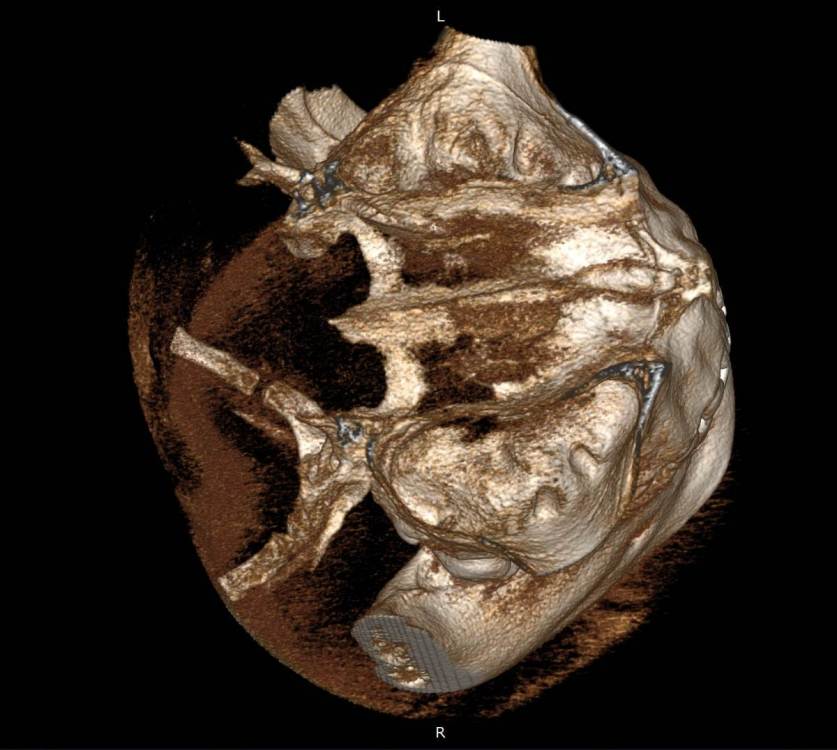

Mnrg Опубликовано 7 июля, 2023 Автор Поделиться Опубликовано 7 июля, 2023 6 минут назад, wladdX сказал: Гайморит у вас совершенно необязательно имеет одонтогенную природу (вызван зубами). Судя по КТ, зуб 16 может быть виновником (а может и не быть). Для уточнения нужна также проверка витальности его пульпы (жив нерв или нет). Если пульпа нежизнеспособна, то этот зуб почти наверняка поддерживает воспалительный процесс в пазухе. Зуб 18 вряд ли нужно трогать. Лежит он себе в кости и пускай, никому он там не вредит. Да он вплотную прилежит к корням зуба 17, но и только. С внешней средой не контактирует. Никакого негативного влияния на соседние зубы он оказывать не должен: формирование корней завершено, потенции к росту и какому-либо движению нет. Удаление зуба 18 в данной ситуации вряд ли оправдано. Процедура не самая простая, но и не запредельной сложности. Шестерку проверяли холодом - чувствует, не знаю, означает ли это жизнеспособность пульпы, но на холод реагировал немного сильней других зубов. Сегодня открыл КТ программой RadiAntViewer и обнаружил в 3D просмотре визуальные признаки нахождения части восьмерки в краю пазухи. Конечно я не могу утверждать, т.к не врач и насколько понимаю это режим моделирования, но все же выглядит убедительно на мой скромный взгляд. Еще один глупый вопрос, если позволите) Возможно ли в шестерке в одном из трех корней воспаление и нерв разрушен, а другие два при этом будут создавать чувствительность, т.е быть "живыми" или же это фантастика? Деньги запросили немалые для нашего региона за депульпацию (13к) поэтому пытаюсь собрать как можно больше информации прежде, чем принимать решения. Ссылка на комментарий